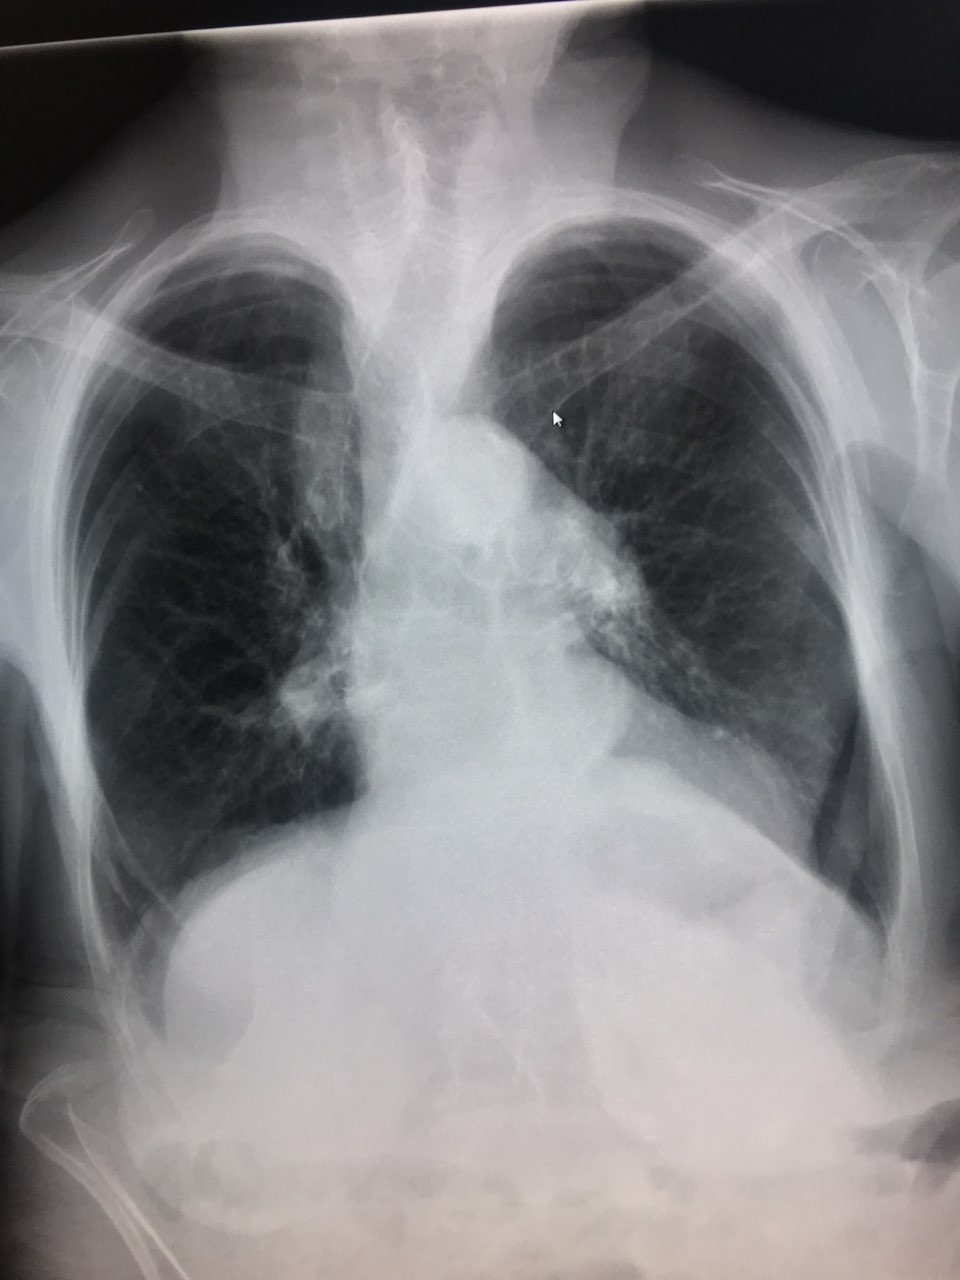

Огнестрельное ранение шеи. Пуля задела спинной мозг, у пациента - квадриплегия (паралич обоих рук и ног)

Огнестрельное ранение шеи. Пуля задела спинной мозг, у пациента - квадриплегия (паралич обоих рук и ног)